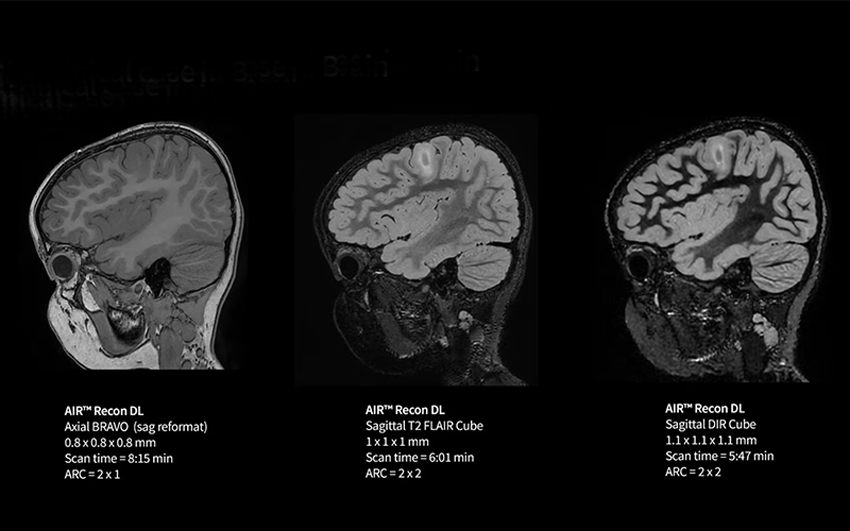

MRI là công nghệ chẩn đoán hình ảnh hiện đại, không sử dụng tia bức xạ, bổ sung hoàn hảo cho CT, X-quang và siêu âm, hỗ trợ phát hiện những bất thường ở não, tim, mạch máu, cơ quan nội tạng…

Kết hợp MRI và CT Scan toàn thân (chỉ có trong gói khám Ningen Dock Bernard) bên cạnh các xét nghiệm chuyên sâu hơn 60 chỉ số, khách hàng có được bộ dữ liệu đầy đủ về sức khoẻ.

Đây là điểm khác biệt cốt lõi trong gói khám Ningen Dock Bernard: quy trình đọc và kiểm tra chéo hình ảnh chưa từng xuất hiện tại Việt Nam.

| Lớp 1 | Bác sĩ Bernard và bác sĩ Bệnh viện Đại học Yamanashi đọc độc lập kết quả MRI và CT, đưa ra báo cáo. | |

| Lớp 2 | Bệnh viện Đại học Yamanashi kích hoạt hội chẩn nội bộ với các trường hợp bệnh lý phức tạp, nghi ngờ ung thư. | |

| Lớp 3 | Hai bên thảo luận chuyên môn thông qua hội chẩn trực tuyến, đưa ra kết luận cho từng trường hợp cụ thể. | |

Bác sĩ Kaori Aoyagi, Bệnh viện Đại học Yamanashi nhận xét về cơ chế kiểm tra chéo: “Dù cách Việt Nam hơn 4.500 km, đội ngũ chuyên gia từ Bệnh viện Đại học Yamanashi luôn đồng hành, cùng kiểm tra kết quả MRI, CT scan trong 100% phiên khám Ningen Dock, tầm soát chuyên sâu ung thư, nguy cơ đột quỵ…; hội chẩn trong những trường hợp cần thiết/có yêu cầu. Quy trình kiểm tra chéo (double reading) giữa các bác sĩ giúp kết quả được xem xét nhiều lớp trước khi đưa ra kết luận cuối cùng”.

Sự tỉ mỉ, cẩn trọng trong việc đọc & đánh giá hình ảnh luôn được chú trọng tại Bernard Healthcare, cũng là nét đặc trưng trong văn hoá y khoa Nhật Bản. Tinh thần này góp phần nâng cao độ chính xác, hạn chế nguy cơ bỏ sót tổn thương, đặc biệt với một số ung thư rất khó phát hiện giai đoạn sớm, những tổn thương tế nhị, mờ nhạt, không điển hình và đồng thời hỗ trợ đưa ra quyết định điều trị phù hợp cho từng khách hàng.